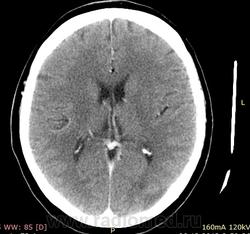

Травма головы 10-12дней назад, женщина, 1975г.,  направленная нейрохирургом, контраст-40мл. в\в. Непонятные изменения на уровне мозолистого тела и слева в затылочной доле. Первое расценено как образование жировой плотности, второе как инсульт.  Не очень внятный для меня инсульт, не абсцедирование ли слева? И что за жир?

Дайкомы не смотрел, по представленным снимкам низкоплотностное образование вокруг мозолистого тела это скорее всего Перикаллозальная липома - http://radiopaedia.org/articles/pericallosal-lipoma

Изменения в левой теменно-затылочной области описал бы как ушиб 1-го вида (по Корниенко).

Вокруг мозолистого тела - это врожденная "липома" мозолистого тела, дисэмбриогенетические изменения. В принципе, при таких размерах это не имеет клинического значения.

В левой затылочной области - это ушиб, скорее всего в зоне противоудара. Посмотрите повнимательнее, тут есть еще ушиб правой лобной доли - в зоне удара.

ну раз была травма в анамнезе, то сомнений нет - ушиб!